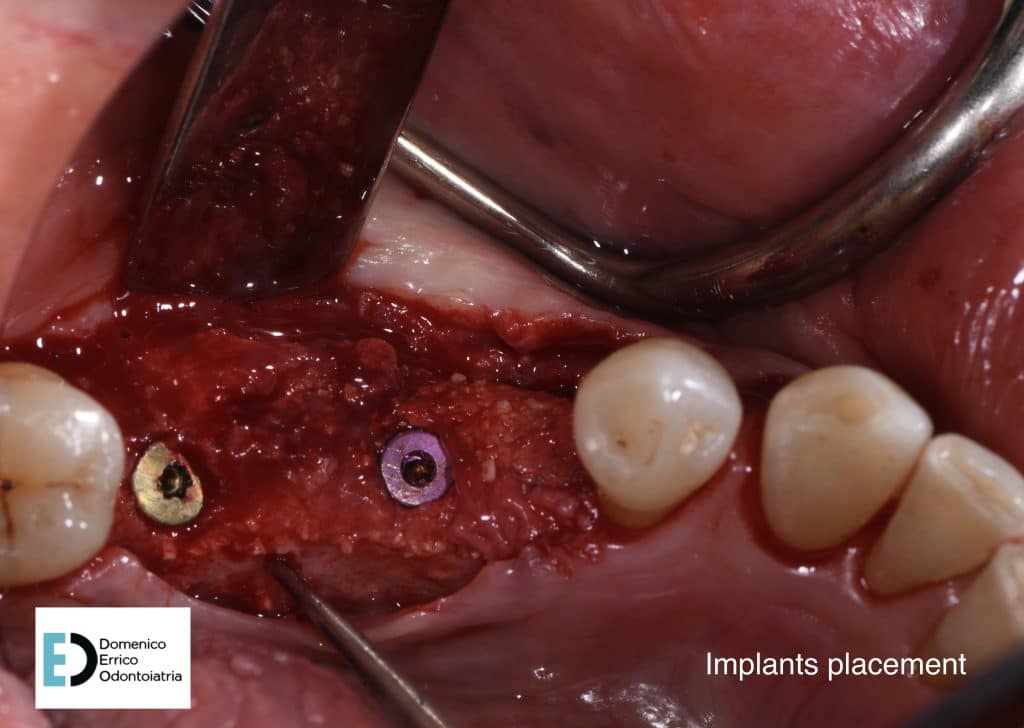

The treatment objectives are primarily functional: the restoration of volumes, necessary for implant rehabilitation due to insufficient bone height for fixture placement applying a mesh with a filler, consisting of 50% autologous bone and 50% heterologous bone; the reinstatement of chewing function by a second intervention to remove the mesh and simultaneously place two implant fixtures, concurrent with an increase of adherent gingival tissue level; and finally, the goal is to achieve the correct vertical relationship between the upper and lower arches through prosthetic rehabilitation of the upper arch with the replacement of the old prosthetic device.